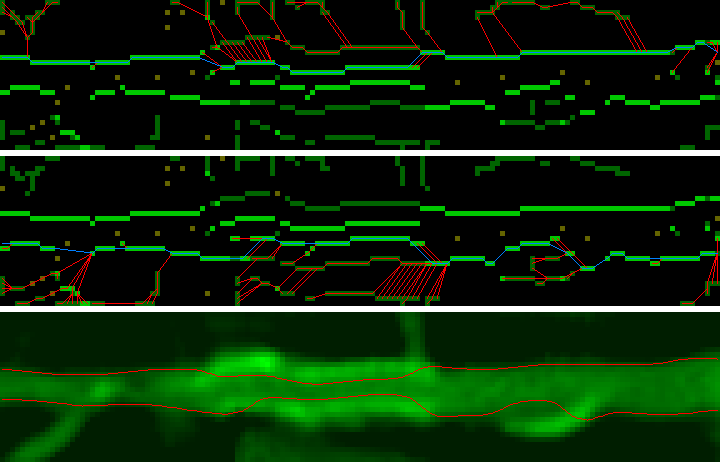

Зеленая линия — гистограмма интенсивностей, красная — полученная математическая модель.

Если визуально отобразить данные согласно порогам, полученным на предыдущем этапе, мы получим такую картину:

Красный цвет — стенка сосуда. Зеленый цвет — просвет. Белый цвет — кальций.

Первое, что бросается в глаза — это “висячий” кальций, который не примыкает ни к одной из стенок. Это считается нормальным и возникает вследствии сглаживания, применяемого самим томографом.

Благодаря такому подходу мы находим просвет сосуда с учетом того, что кальций не примыкает вплотную к стенкам. Теперь просто объединяем результаты со всех срезов и получаем внутреннюю и внешнюю границы сосуда:

Кажущаяся неточность границы после стента вызвана аномальным раздвоением: